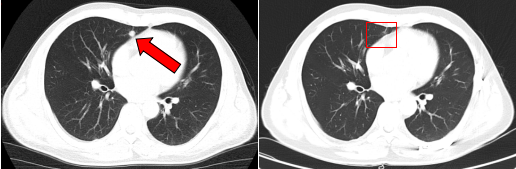

治疗前后的肺部转移病灶图像对比( 左:治疗前,右:治疗后)